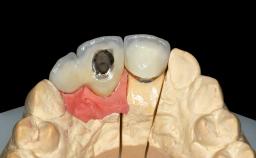

A 45-year-old woman was referred for management of an infection associated with two implant-supported crowns replacing the maxillary central incisors. Two tissue-level implants had been placed and restored with cemented single metal-ceramic crowns in those sites 4 years previously. The patient presented with a draining sinus (i.e. a pathological duct from an abscess cavity to a surface) 3 mm from the midfacial peri-implant mucosal margin of the maxillary right implant crown. She was in good general health, did not smoke, showed a good oral hygiene status, and had no history of periodontal disease. The implants were well positioned. While the patient was very satisfied with the appearance of her crowns, she had noted that the peri-implant soft tissue had receded since their insertion and was concerned about the possibility of further recession.

| Retention | Cemented, with prosthesis margin < 3mm submucosal Cemented, with prosthesis margin < 3mm submucosal |

| Provisional Implant-Supported Prosthesis | Prosthodontic margin < 3 mm apical to mucosal crest Prosthodontic margin < 3 mm apical to mucosal crest |